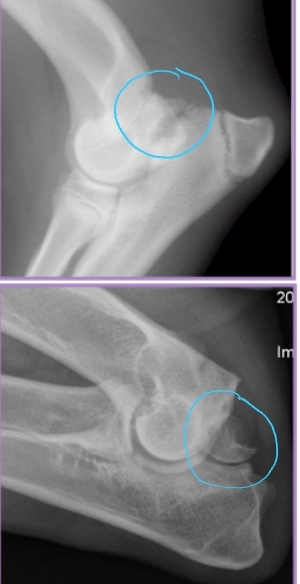

Elbow Incongruity

Et: Asynchronous growth of radius and ulna

Dt: radiographs

Tx: Corrective ulnar ostectomy (short radius syndrome)

Redistribute stress in joint

Allow bone alignment at joint level

Decrease joint stress